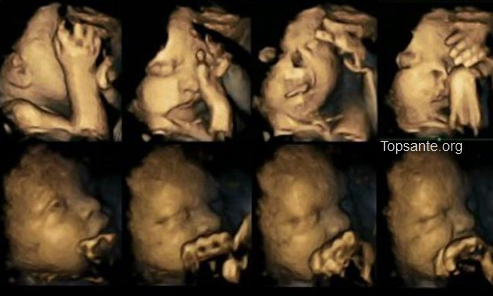

Ces images dérangeantes et difficiles à regarder encourageront peut-être les femmes enceintes à ne pas fumer pendant leur grossesse.

Une étude britannique a révélé l’impact de la cigarette sur le foetus en réalisant une échographie du foetus lorsque la mère fume.

Les photos d’en bas montrent un foetus lorsque la mère ne fume pas. Celles d’en haut montrent un foetus dont la mère fume. Les images parlent d’elles-mêmes :

Le bébé a clairement l’air dégoûté au point de grimacer de douleur. Il frotte ses mains sur son visage et a aussi l’air plus angoissé et stressé. Au contraire, le bébé d’en bas paraît calme et serein.

Selon l’étude menée par des chercheurs anglais, les bébés dont la mère a fumé pendant la grossesse présentent des retards de développement du système nerveux central. Les foetus peuvent également souffrir de problèmes respiratoires. La cigarette peut aussi conduire à des naissances prématurées, voire à la mort du foetus.